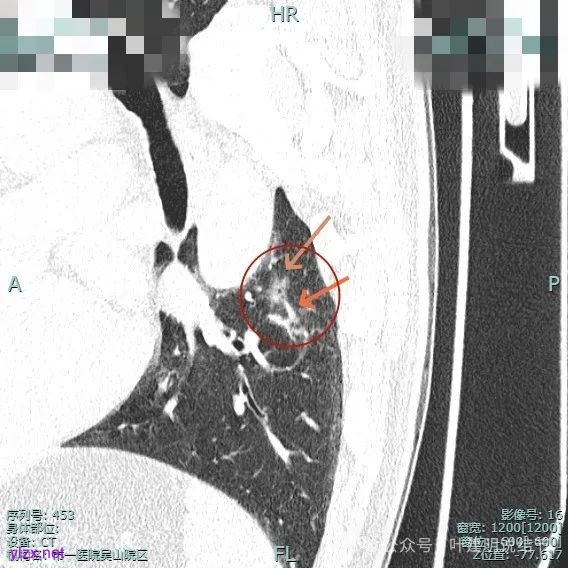

主病灶位于下叶后基底段下肺静脉水平,次病灶在同一层面位靠外基底段交界附近。

靶重建后见主病灶密度不均,灶内混合密度,整体轮廓较为清楚,表面不平,整体有一定膨胀感。

表面有浅分叶征,整体轮廓清。

灶内小空泡征,边缘略显毛糙,整体轮廓较清。

主病灶血管进入,灶内空泡,表面浅分叶,整体轮廓较清。